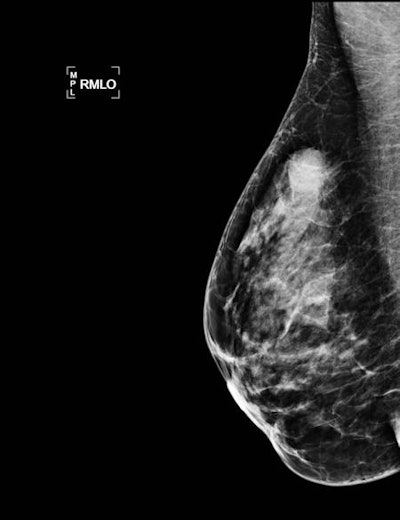

A 33-year-old woman with 15-mm palpable lump in right breast. Top: Mammogram (mediolateral oblique view) shows an oval-shaped mass with indistinct margins. Bottom: Sonogram with shear-wave elastography shows a round mass with hypoechogenicity, abrupt interface, posterior acoustic enhancement, and a low color rating. All the benign criteria (oval mass, circumscribed margin, etc.) are not filled for fibroadenoma. This is categorized as BI-RADS 4. Biopsy under ultrasound guidance: grade III triple-negative (TN) ductal invasive carcinoma (estrogen-negative, progesterone-negative, HER2-negative cancer). TN cancers may have pseudobenign imaging features and be classified BI-RADS 3.